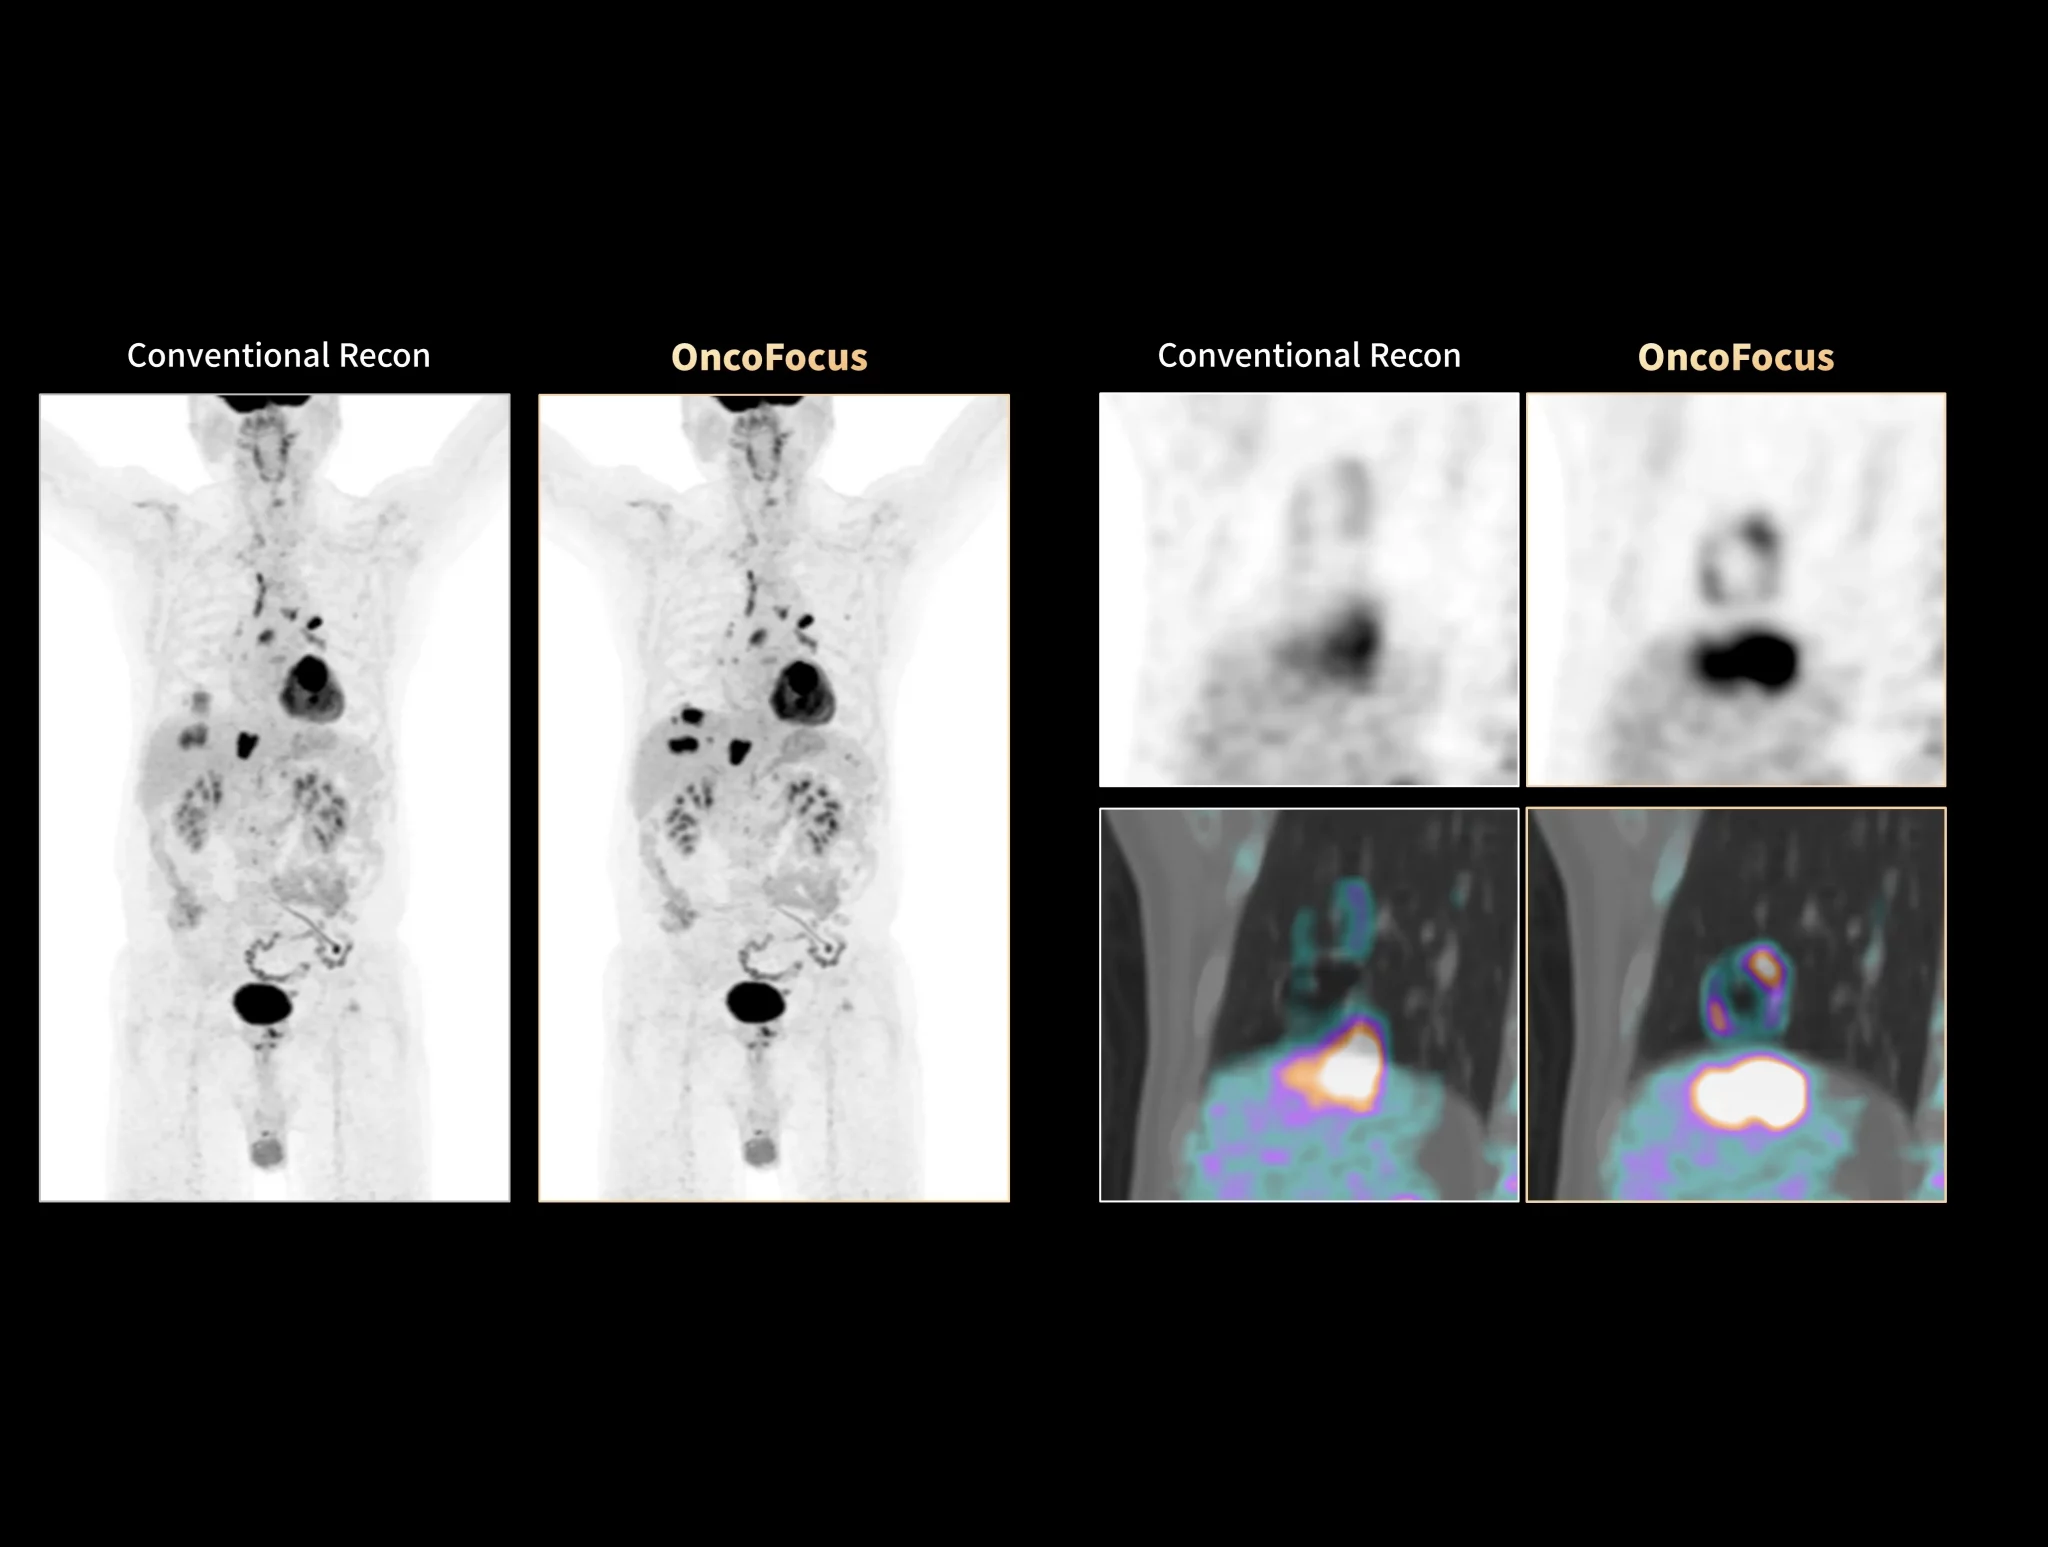

uMI Panorama is greatly empowered by innovative technologies integrated into the uExcel SCAN and uExcel CARE workflows. With uExcel SCAN, you can rely on intelligent positioning, scanning, and motion correction to streamline your routine tasks and maximinze your work efficiency. And uExcel CARE features uExcel DPR and uExcel AIIR reconstruction algorithms to ensure clear images even at low doses.

Unlock New Possibilities for Exploration

With the ultra-high system performance, uMI Panorama faces up to the challenges of tracers with different half lives and the complex scanning conditions, without compromise for image quality.